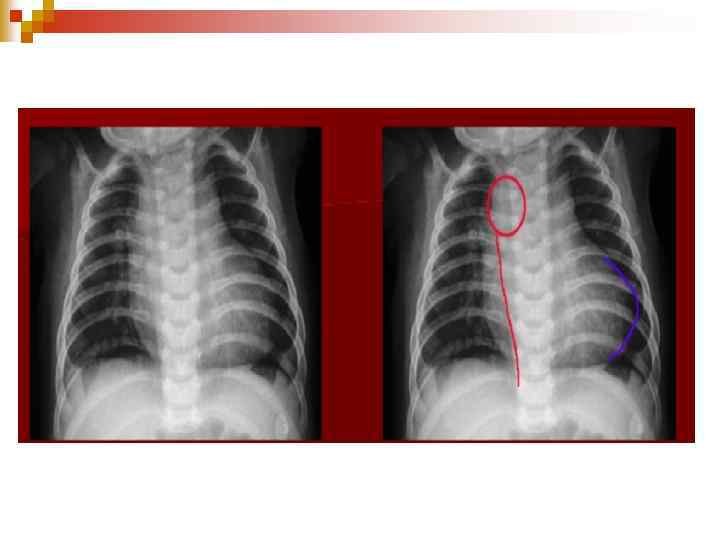

ЕКГ n Гіпертрофії правого шлуночка (RVH) Правий Кут нахилу осі Блокада правої ніжки пучка Гіса ДМПП

ДМПП